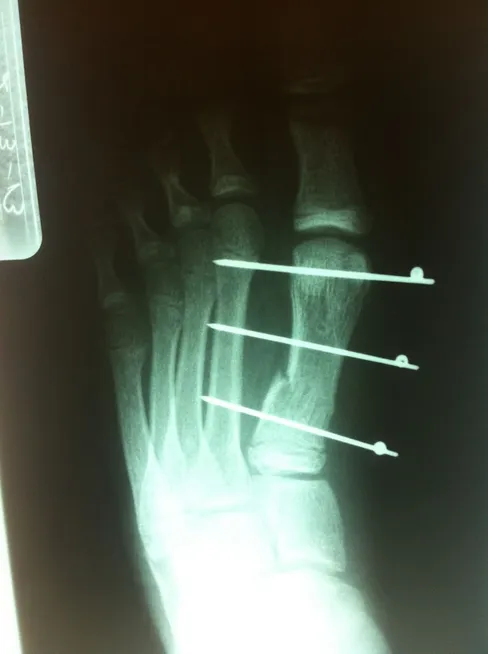

This is post-operative x-ray of a repair of a fracture of the long bone of foot connected to the great toe, There are three pins holding the fracture fragments in place, and once this heals the pins are removed.